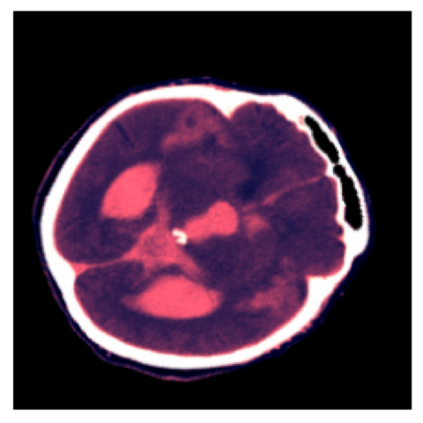

We present an effective method for Intracranial Hemorrhage Detection (IHD) which exceeds the performance of the winner solution in RSNA-IHD competition (2019). Meanwhile, our model only takes quarter parameters and ten percent FLOPs compared to the winner's solution. The IHD task needs to predict the hemorrhage category of each slice for the input brain CT. We review the top-5 solutions for the IHD competition held by the Radiological Society of North America(RSNA) in 2019. Nearly all the top solutions rely on 2D convolutional networks and sequential models (Bidirectional GRU or LSTM) to extract intra-slice and inter-slice features, respectively. All the top solutions enhance the performance by leveraging the model ensemble, and the model number varies from 7 to 31. In the past years, since much progress has been made in the computer vision regime especially Transformer-based models, we introduce the Transformer-based techniques to extract the features in both intra-slice and inter-slice views for IHD tasks. Additionally, a semi-supervised method is embedded into our workflow to further improve the performance. The code is available in the manuscript.

翻译:我们在RSNA-IHD竞争(2019年)中提出了一种有效的内爆出血检测方法(IHD),该方法超过了获胜者解决方案的绩效(RSNA-IHD 竞争(2019年),同时,我们的模型与获胜者解决方案相比,仅需要四分之一参数和10%的FLOP;国际HD的任务需要预测输入大脑CT的每个切片的出血类别。我们审查了北美辐射协会(RSNA)在2019年举办的IHD竞赛的5级顶级解决方案。几乎所有顶级解决方案都依靠2D共流网络和相继模型(双向GRU或LSTM)来提取虱内和肺间特征。所有顶级解决方案都通过利用模型共性能提高性能,而在过去几年中,模型数从7到31不等。由于计算机视觉系统,特别是以变压器为基础的模型取得了很大进展,因此我们采用了基于变压器的技术来提取IHDD任务的内切和相间观点的特征。此外,半超式方法已经嵌入我们的工作流程。